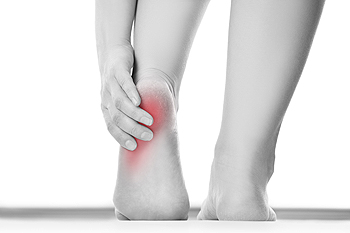

If you have consistent pain and discomfort in the heel of your foot, you may have a medical condition that is referred to as plantar fasciitis. It will typically target people who are active in running sports, or for those who stand for the majority of the day. This ailment is a result of inflammation that occurs in the long portion of tissue that runs along the bottom of the foot, which links the toes to the heel, and this is known as the plantar fascia. A common symptom of this ailment is severe heel pain, which may often be worse in the morning when the first steps are taken. Some patients have specific tendencies that may encourage the development of this condition, including being overweight, wearing shoes that do not fit correctly, or are born with flat feet or high arches. There are possible techniques that may offer moderate relief, and these may include performing proper foot stretches, resting your feet as often as possible, or wearing shoe inserts. If you have developed this condition, it’s suggested to speak with a podiatrist to understand what treatment options are correct for you.

Plantar fasciitis is a common foot condition that is often caused by a strain injury. If you are experiencing heel pain or symptoms of plantar fasciitis, contact Brent Harwood, DPM from Southeast Podiatry. Our doctor can provide the care you need to keep you pain-free and on your feet.

What Is Plantar Fasciitis?

Plantar fasciitis is one of the most common causes of heel pain. The plantar fascia is a ligament that connects your heel to the front of your foot. When this ligament becomes inflamed, plantar fasciitis is the result. If you have plantar fasciitis you will have a stabbing pain that usually occurs with your first steps in the morning. As the day progresses and you walk around more, this pain will start to disappear, but it will return after long periods of standing or sitting.

What Causes Plantar Fasciitis?

There are some risk factors that may make you more likely to develop plantar fasciitis compared to others. The condition most commonly affects adults between the ages of 40 and 60. It also tends to affect people who are obese because the extra pounds result in extra stress being placed on the plantar fascia.